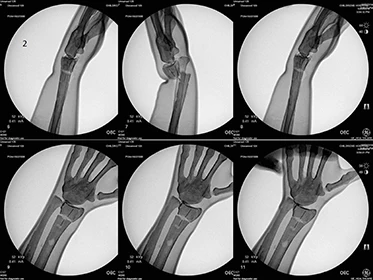

This multi-discipline trainer allows users to incorporate manual reduction with real time fluoroscopic visualization.

- Soft tissue arm model with radiopaque coated bones and a multi-position universal bed rail clamp allowing the user to train in the most common patient positions.

- The tactile hands-on feel and real-time imagery enhance the user experience. The reduction model allows palpation of internal structures through the soft tissue before and during reduction.

- Traditional roll on casting with manual reduction with or without finger traps can be performed.

- The radius bone has alignment guide lines to allow the user to assess the accuracy of the reduction after cast application. Casting materials can be removed using standard cast removal techniques.